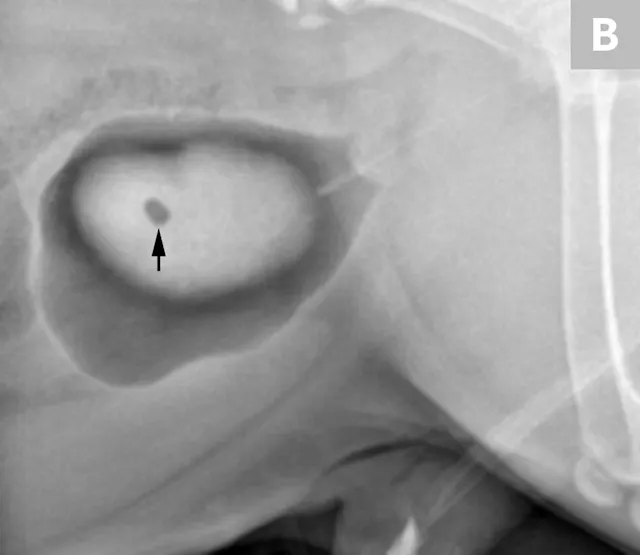

A separate center of ossification associated with the os penis may mimic a urethral calculus (Figure 11 A and B). A separate center of ossification can be seen at either end of the os penis and will be in line with the os penis. A calculus within the penile urethra would be seen ventral to the os penis in the location of the urethra. Contrast urethrography can be a helpful way to differentiate between a separate center of ossification and urethral calculus (Figure 11C).

FIGURE 11A

Lateral radiograph of a male dog collimated to include the urinary bladder and os penis. Note the well-defined mineral opacity just proximal to and at the same level as the base of the os penis—a separate center of ossification (arrow). Also note the two soft tissue opaque nodules summating with the prepuce, presumed to be small nipples (arrowheads).